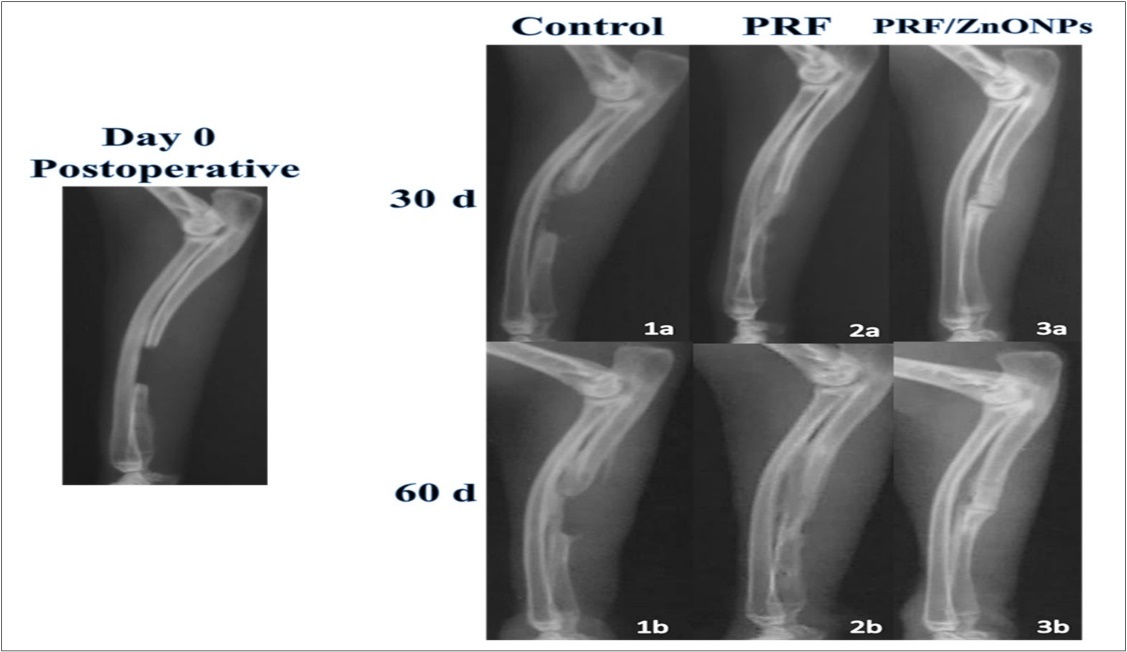

During the current study, no serious complications and death were observed and the healing took place in all surgical wounds by the first intention. Clinical wellness was observed in all rabbits as early as the second postoperative day. Compared to the postoperative radiographs, the addition of PRF and ZnONPs to segmental ulnar CSD of 12-mm length resulted in obvious radiographic changes (Table 1, Figure 2), and the statistical analysis showed a significant difference in the healing score between the three experimental groups (P = 0.000) at all-time points (P = 0.000- 0.003) during the study.

Figure 2.Showing lateral radiographs of the three experimental groups (Control, PRF and PRF/ZnONPs) at 0, 30 and 60 postoperative days.

Concerning bone healing in the region of interest, treatment of CSD by adding PRF either alone (PRF group) or in combination with ZnONPs (PRF/ZnONPs group) resulted in a highly significant (P = 0.000) increase in the healing score of CSD versus the Control group. On the 30th postoperative day, the healing score was 3.0 (2.0- 3.0) and 4.0 (4.0- 4.0) in PRF and PRF/ZnONPs groups respectively versus 2.0 (1.0- 2.0) in the Control group. On the 60th postoperative day, complete filling of the CSD represented by 0.4 healing scores was observed in both treatment groups, versus 2.0 healing score and incomplete filling in the Control group.

In terms of bridging callus, there was a significant difference between times within a group (P = 0.000- 0.001) but a non-significant difference between groups within time. On the 30th day, 62.5% of rabbits in both treatment groups showed gap bridging versus no bridging in the control group with a significant difference (P = 0.018) between groups within this time point. At the end of the study, 75% of the control group rabbits started to show some sort of bridging callus meanwhile all rabbits of both PRF and PRF/ZnONPs groups exhibited complete bridging of the gap.

Comparing the radiographic density of the healed bone, both treatment groups exhibited higher bone density compared to the Control group. In all rabbits of the combination group, maximal density was early obtained on the 30th postoperative day.